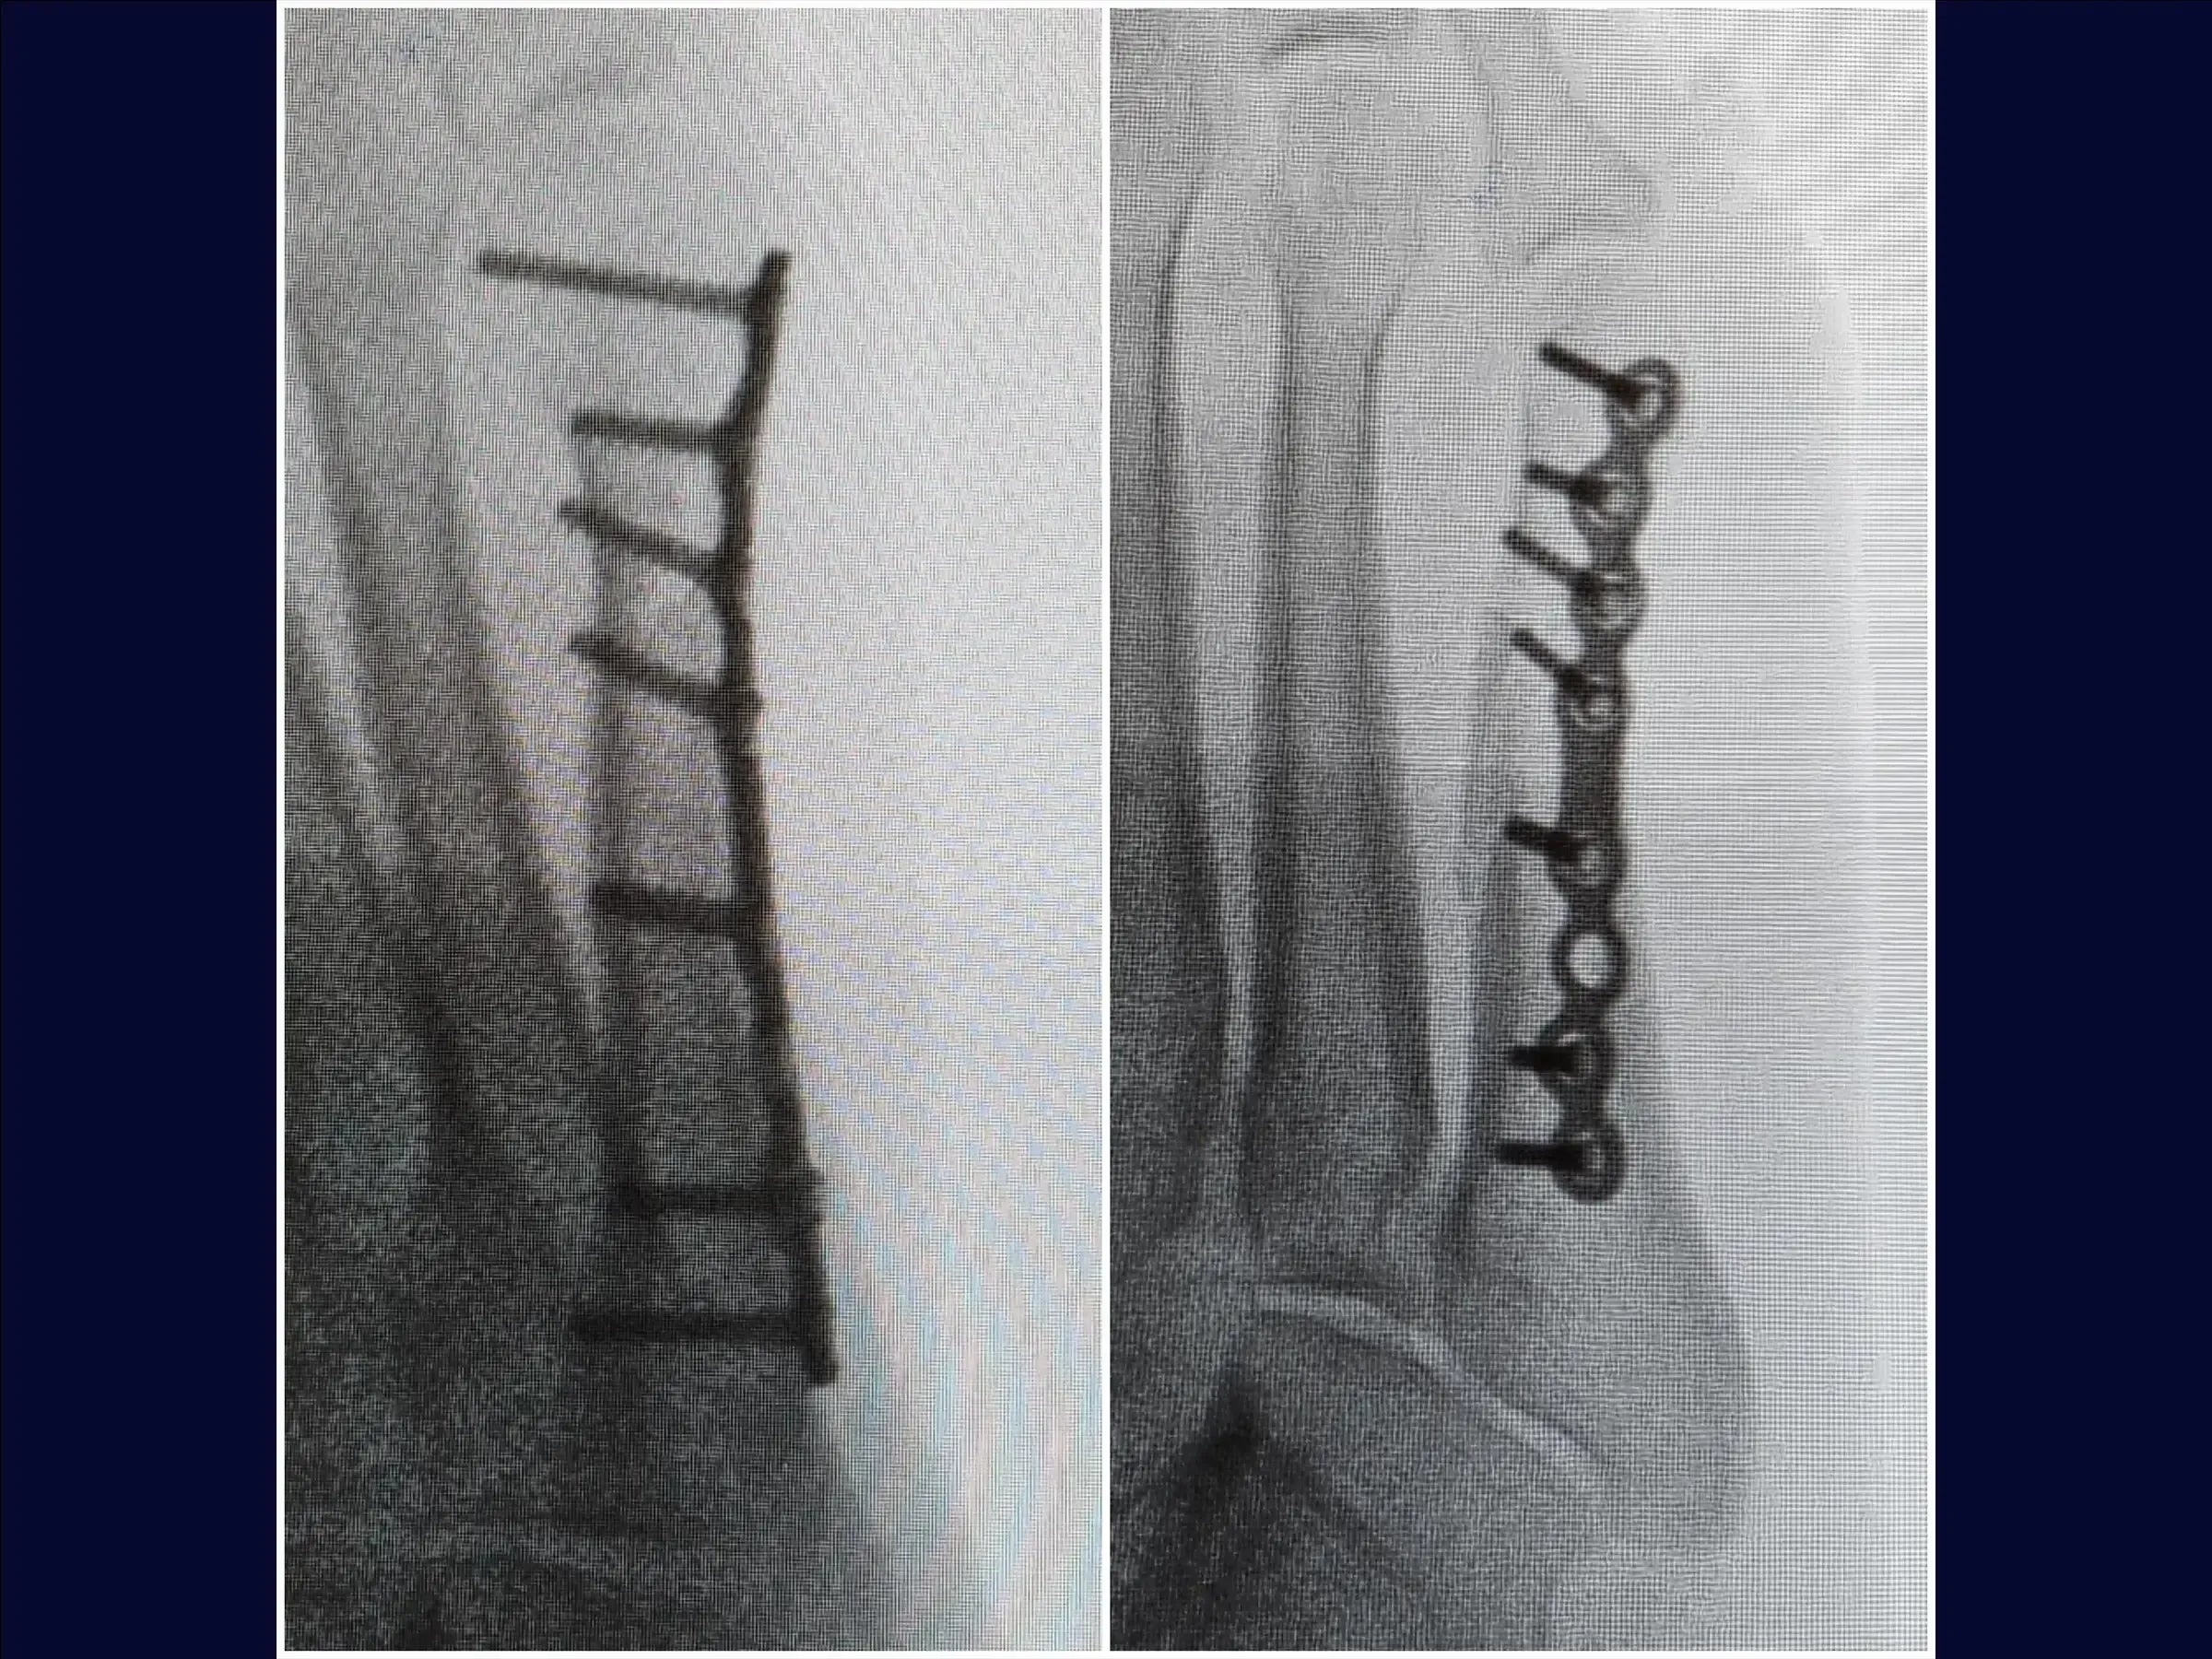

Mejore sus habilidades en el tratamiento quirúrgico de fracturas desplazadas del quinto metatarsiano. Este procedimiento requiere una reducción anatómica cuidadosa para evitar la metatarsalgia o la disfunción de la marcha, especialmente en pacientes jóvenes y atletas. Esta capacitación detalla el procedimiento quirúrgico con placa de bloqueo y tornillos, con énfasis en la rápida recuperación funcional y el retorno a la actividad deportiva.

- Tratamiento quirúrgico de las fracturas desplazadas del quinto metatarsiano.

- Reducción anatómica y fijación estable con placa de bloqueo.

- Reducción de la fractura y estabilización provisional: Identificación de los vértices de la fractura, reducción bajo visualización directa con pinza de reducción y estabilización provisional con agujas de Kirschner, evitando la zona de la futura placa.

- Fijación Definitiva con Placa Bloqueada: Colocación de una placa minifragmentaria de perfil bajo, utilización de tornillos largos para una adecuada distribución de la carga y reducción de la necesidad de futuras extracciones.